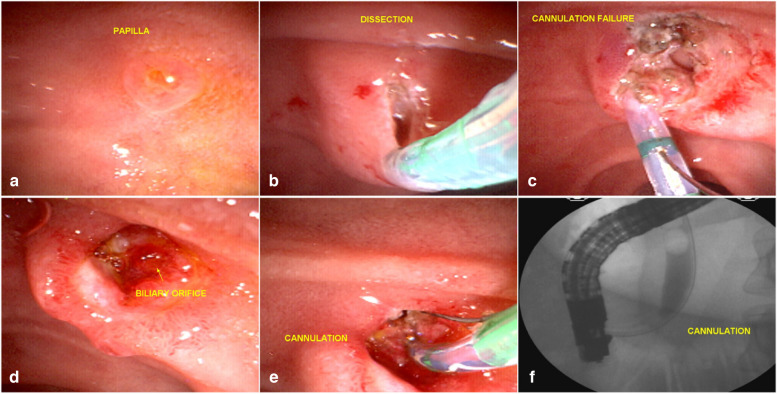

However, in 63 cases (EFP failure), the guidewire was not passed into the common bile duct, most of the time due to minor bleeding or edema and loss of identification of structures in the dissection area. These cases were considered failure of the EFP in the first attempt. Of these 63 patients, 33 returned for a second attempt and what we found was a biliary fistula, with an easily identified orifice allowing the passage of the guide wire and the sphincterotome. However, in 30 cases, the patients did not return for the second attempt for various reasons. The reasons for non return were, worsening of the biliary obstruction or the clinical condition of the patient, complications of the underlying disease, the decision of the surgeon who conducted the case, and the indication of other alternatives for biliary drainage. As a result, 30 EFP patients did not return for the second attempt. Most of these cases were advanced cancer of the head of the pancreas that did not allow the guide wire to pass through the tumor. Such patients were referred for endoscopic ultrasound-guided biliary drainage, percutaneous transhepatic drainage or surgery.

According to Flumignan [ref. 18] and Deng [ref. 19], a second fistulotomy attempt is feasible, and safe, and can be attempted after a short 48-hour interval if the first ERCP attempt is unsuccessful.

This reinforces the idea that suprapapillary dissection is safer than countless unsuccessful attempts at cannulation through the ostium. The occurrence of acute post-ERCP pancreatitis is more dangerous than the sporadic occurrence of mild bleeding from papillary dissection, which is generally easily controlled. Another important point of the EFP procedure is that the wide exposure of the structures of the papilla leads to the formation of a fistula that, in most cases, is easily visualized by staining the bile around the fistular orifice, facilitating the cannulation of the bile duct (Fig. 6).